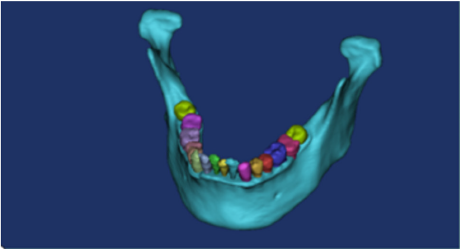

The CT scan image was imported into Mimics 19.0 software. Adjusted the image gray value to generate a 3D model (Figure 1). Three points were selected on the surface of the mandible to establish a reference plane, and this was then used to draw a sketch to segment and simulate the mandibular defect. According to the clinical size of the titanium plate, the model was established and saved in the SLDPRT format. In the geometry, the mandibular cortical bone, mandibular cancellous bone, fibula, teeth, titanium plates and titanium nails were given relevant materials. In order to ensure the accuracy of the calculation, the type and size of the model grid was controlled, and the contact position grid was refined. The grid type was set to a 10-node tetrahedral grid. The boundary conditions and loads were set. Finally, three-dimensional finite element models of the normal mandible and four types of defects were established.